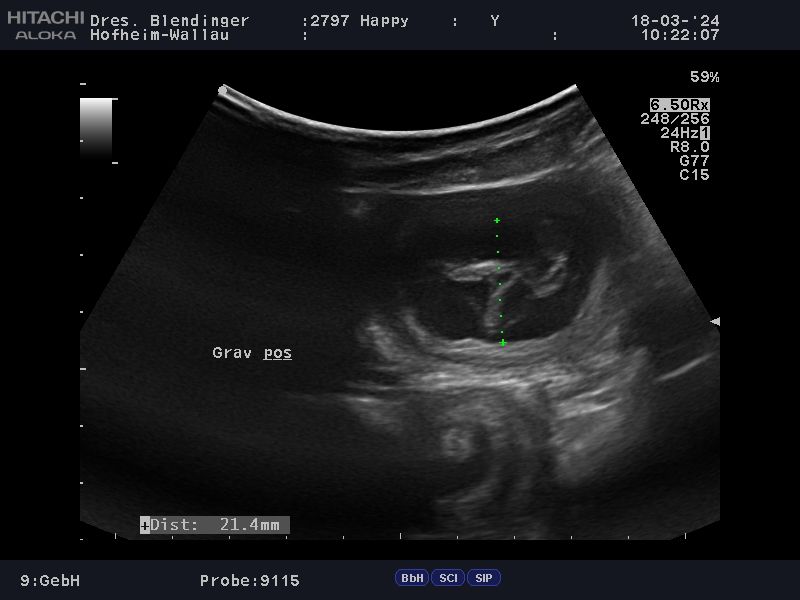

Das, was wir schon vermutet hattten, wurde uns heute, durch unseren Tierarzt bestätigt: Happy"ist trächtig . Wir werden um den 20.04.2024 Welpen in noir bekommen. Es wird für Happy ihr  letzter Wurf sein. Sie hat immer große Würfe gehabt und hat diese problemlos großgezogen. Wir hoffen und wünschen uns das es bei ihrem letzten Wurf auch so schnell, geht wie bei ihren beiden ersten Würfen. Namen mit L werden diesmal gesucht, drei Namen stehen schon fest La Luna , Le Soleil un L´Jiott. Nun haben wir noch ein paar Wochen vor uns und die Vorbereitungen können  beginnen